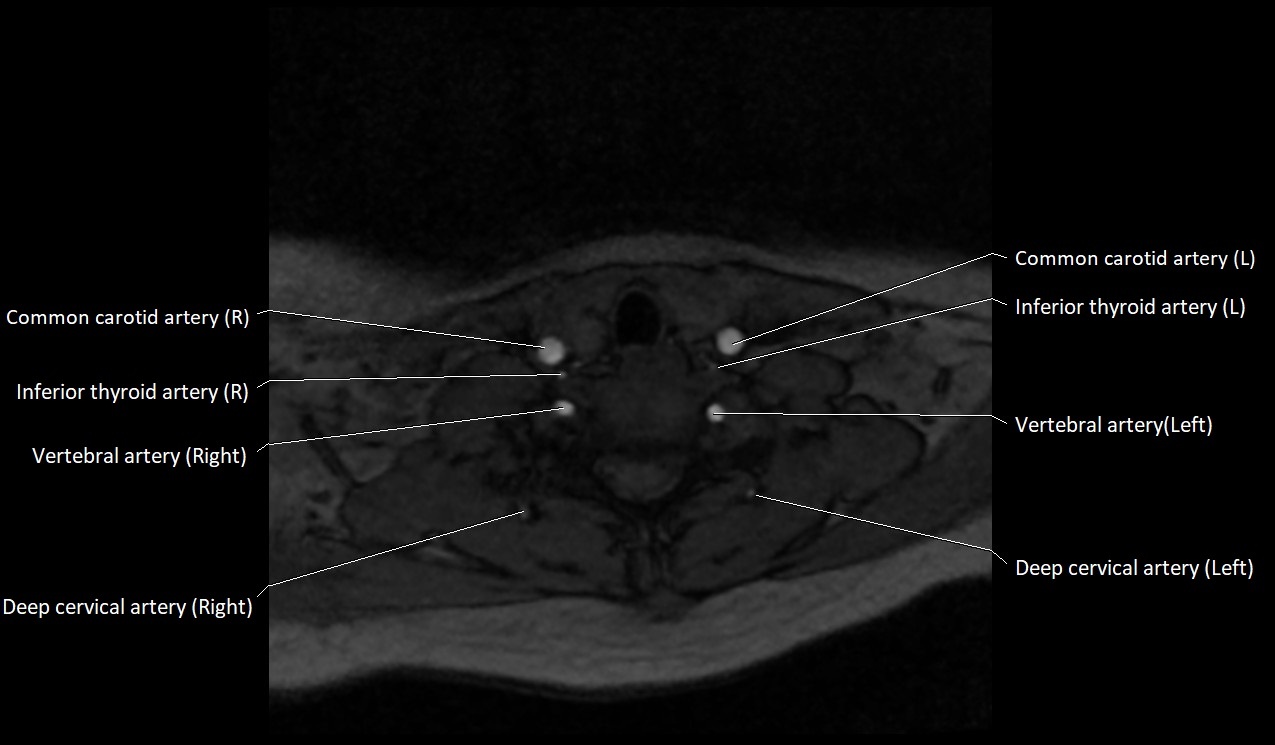

MRI Appearance:

• T1-Weighted Images:

• Appears as a tubular, hypointense (dark) structure relative to muscle

• May show flow void if the blood flow is fast

• T2-Weighted Images:

• Typically hypointense or isointense to muscle, but can be hyperintense if slow flow or stasis is present

MRI images